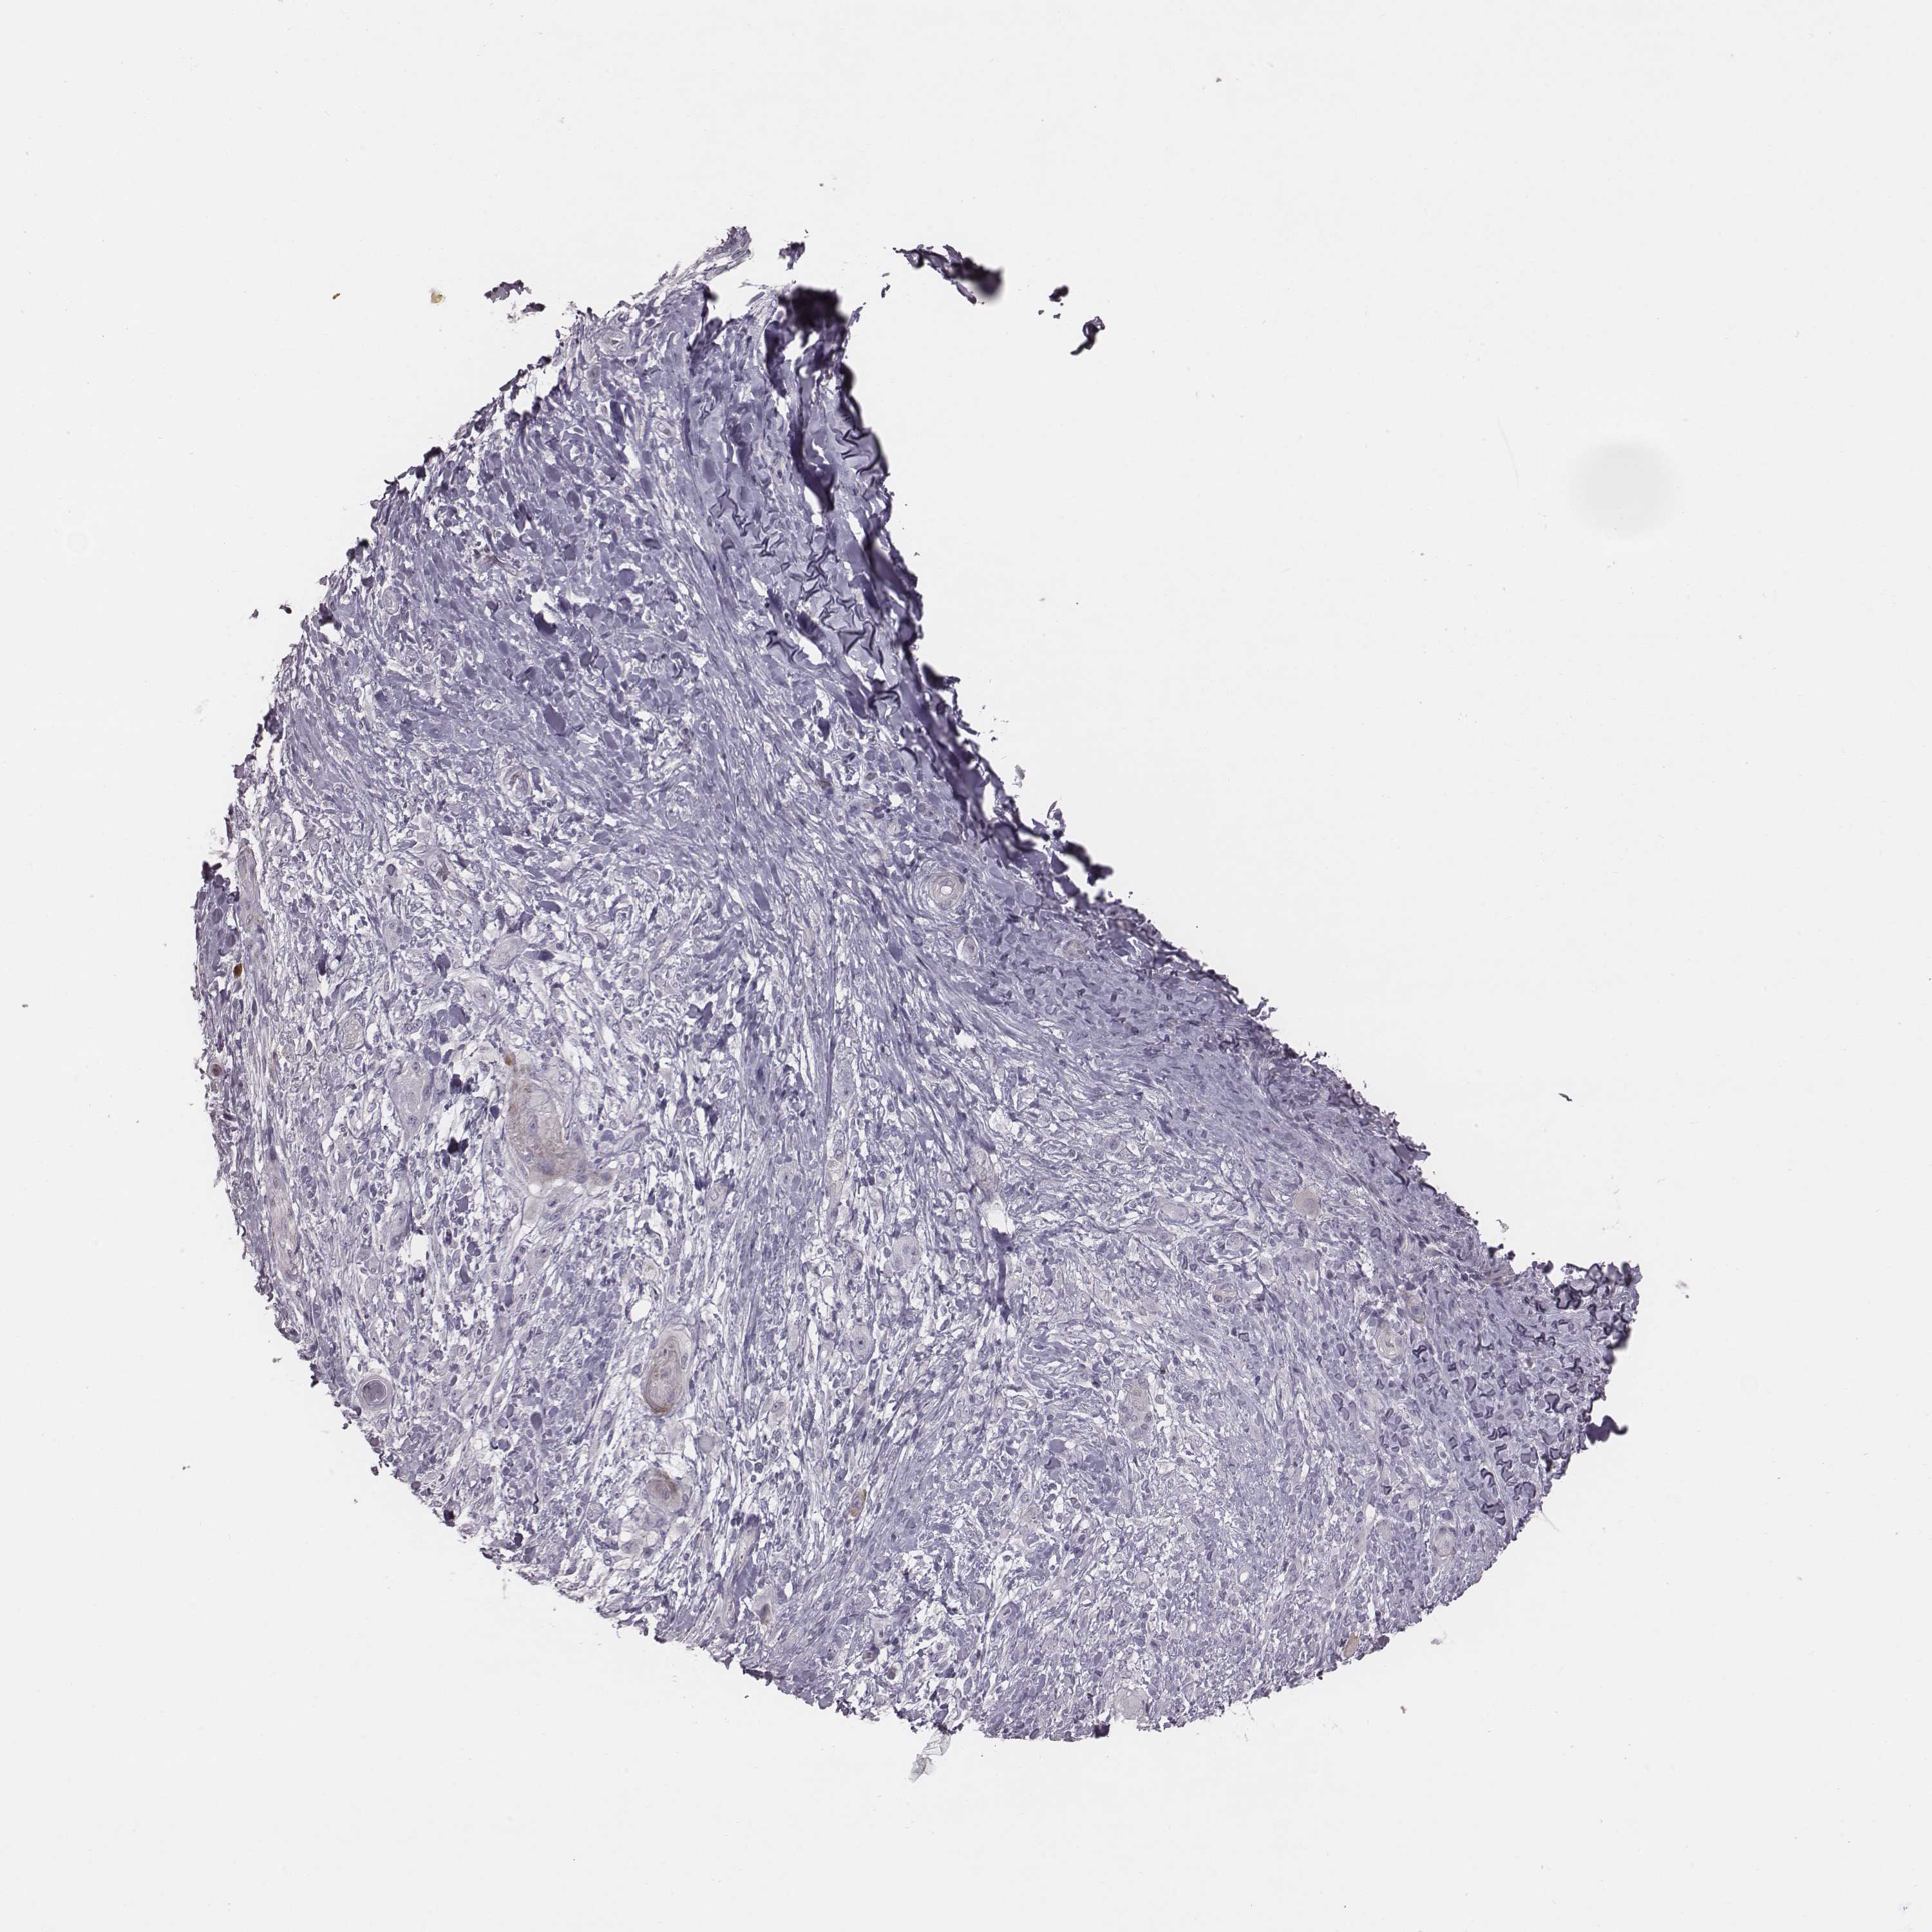

Basal cell and squamous cell cancer

SKIN CANCER - Protein expressioni

A mouse-over function shows sample information and annotation data. Click on an image to view it in a full screen mode. Samples can be filtered based on level of antibody staining by selecting one or several of the following categories: high, medium, low and not detected. The assay and annotation is described here.

Antibody stainingi

Antibody staining in the annotated cell types in the current human tissue is reported as not detected, low, medium, or high, based on conventional immunohistochemistry profiling in selected tissues. This score is based on the combination of the staining intensity and fraction of stained cells.

Each image is clickable and will lead to virtual microscopy that enables deeper exploration of all samples and also displays staining intensity scores, fraction scores and subcellular localization as well as patient and tissue information for each sample.

Antibody HPA036912

Staining

High

Strong

Quantity

Location

Basal cell carcinoma